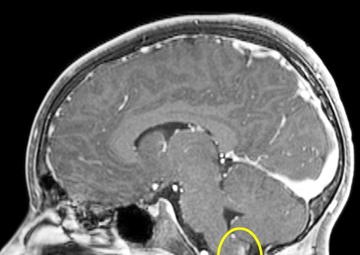

Troy Brock’s, 8, MRI’s are composites showing the progress of his Ganglioglioma after 6 months of Targeted therapy treatment from October 25, 2021 to May 3, 2022. It is important to note that among the shrinking tumor it can be seen that less of the cancer cells absorb the contrasting dye indicating that the cancer cells are dying off, according to Troy's Neuro Oncologist. (Courtesy photos......